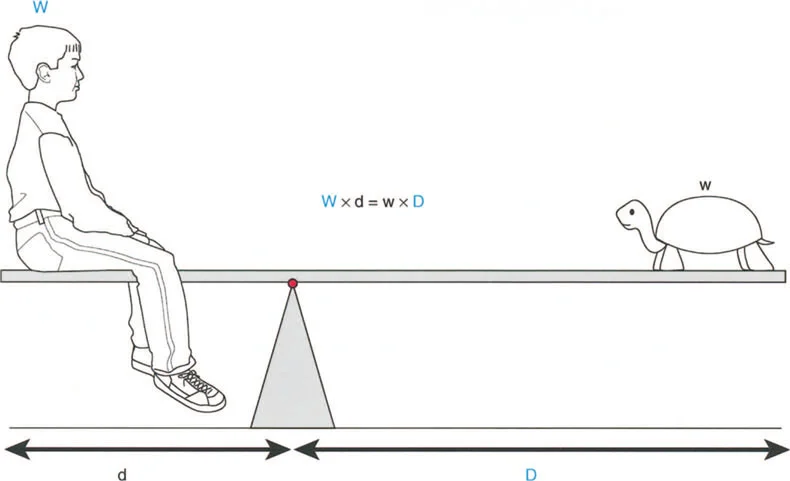

يشير خلل وظيفة الذراع الرافعة إلى التغيير المرضي في علاقات الرافعة الطبيعية بين ثلاثة مكونات حاسمة:

1. الحمل (The Load): الوزن أو المقاومة التي يجب التغلب عليها.

2. الجهد (The Effort): القوة العضلية المطبقة لتحريك الحمل.

3. موضع نقطة الارتكاز (The Fulcrum Position): المفصل الذي يحدث حوله الدوران.

بشكل خاص، يصف خلل وظيفة الذراع الرافعة حالة سريرية تتشوه فيها أذرع الرافعة الداخلية و/أو الخارجية بسبب سوء محاذاة العظام، أو التشوهات الالتوائية، أو تيبسات المفاصل الموضعية.

تاريخياً، كان جراحو العظام بطيئين في إدراك الأهمية القصوى لخلل وظيفة الذراع الرافعة، وغالبًا ما كانوا يركزون فقط على تحرير الأنسجة الرخوة أو نقل الأوتار. غالبًا ما يؤكد التدريب الجراحي على التفكير في العضلات على أنها مجرد مولدات طاقة بيولوجية. ومع ذلك، فإنه قانون أساسي في الفيزياء أن الطاقة لا يمكن توليدها أو نقلها أو استخدامها دون الاستفادة من أذرع الرافعة الهيكلية التي تتصل بها تلك العضلات.

بمجرد أن يبدأ الجراح في التفكير من حيث "العزوم" التي تولد القوة، بدلاً من مجرد انقباض عضلي معزول، فإنه يبدأ تلقائيًا في فحص النصف الآخر من المعادلة الميكانيكية: الرافعة نفسها.

بينما لا يستطيع الطب الحديث فعل الكثير لزيادة القوة البيولوجية الخام التي تولدها العضلة بشكل دائم (بخلاف العلاج الطبيعي)، يمكن غالبًا زيادة حجم العزم المؤثر على المفصل بشكل كبير ببساطة عن طريق تصحيح خلل وظيفة الذراع الرافعة جراحيًا. هذا هو جوهر النهج الذي يتبعه الأستاذ الدكتور محمد هطيف في علاج التشوهات العظمية المعقدة، حيث يركز على استعادة الميكانيكا الحيوية السليمة للجسم.